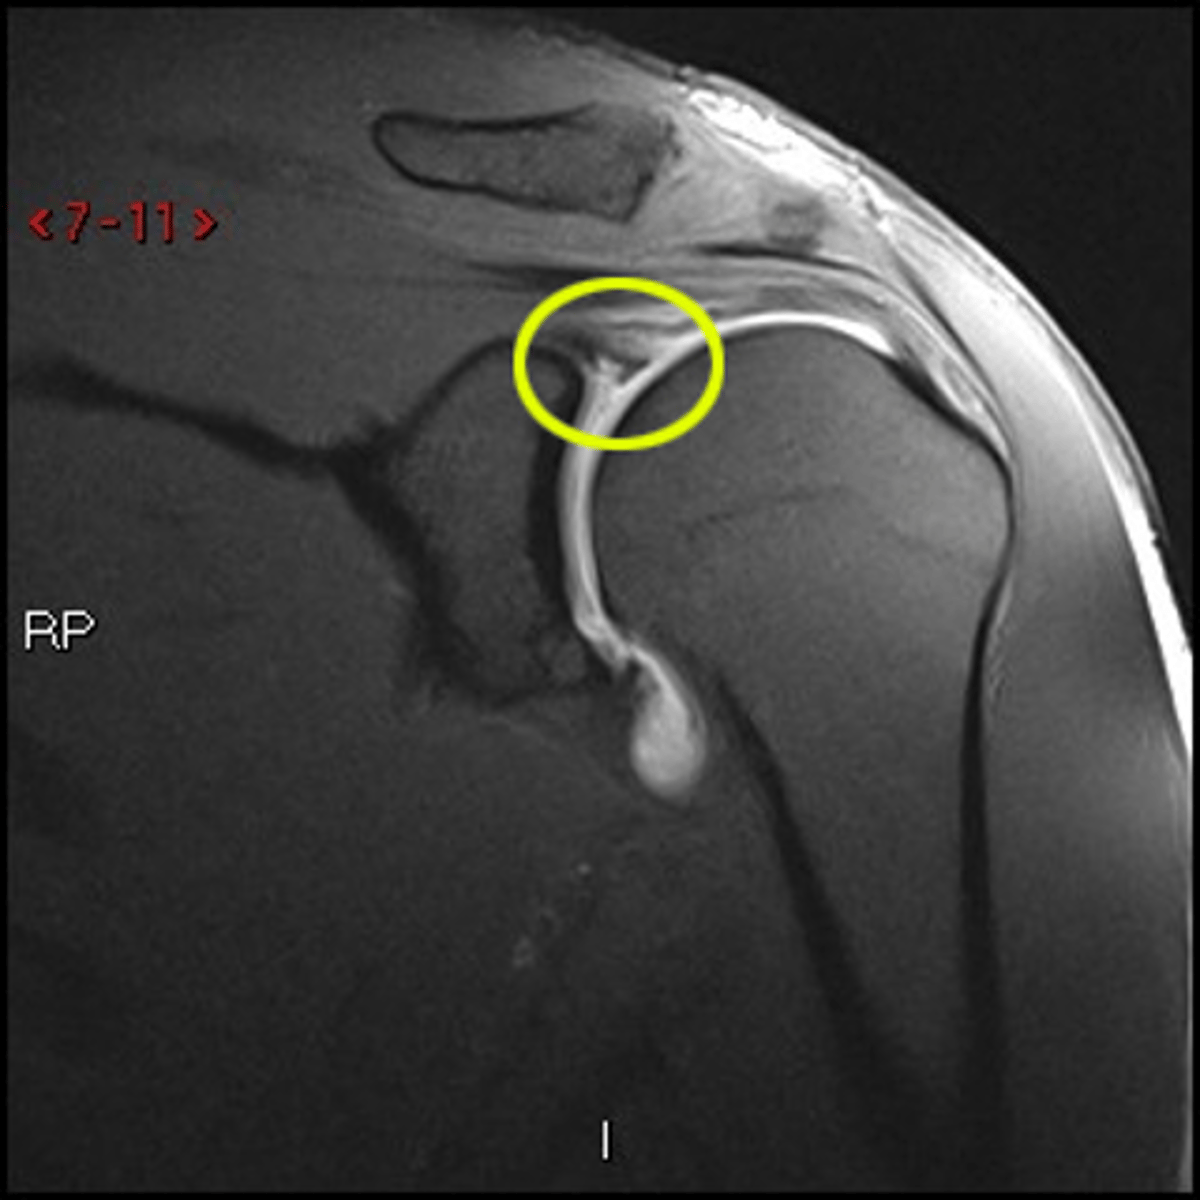

1. When there is a labral tear, the dye will make its way into that region, as depicted in this image

2. ADHESIVE CAPSULITIS IS NOT PRESENT -- THIS IS A NORMAL PRESENTATION DUE TO THE DYE IN THE RECESS

Two questions for you on this one: why do we know there a labral pathology present? (1) and why is this NOT adhesive capsulitis? (2)

Labral tears -- dye is creeping into the labral region

What are these images depicting? How do you know?